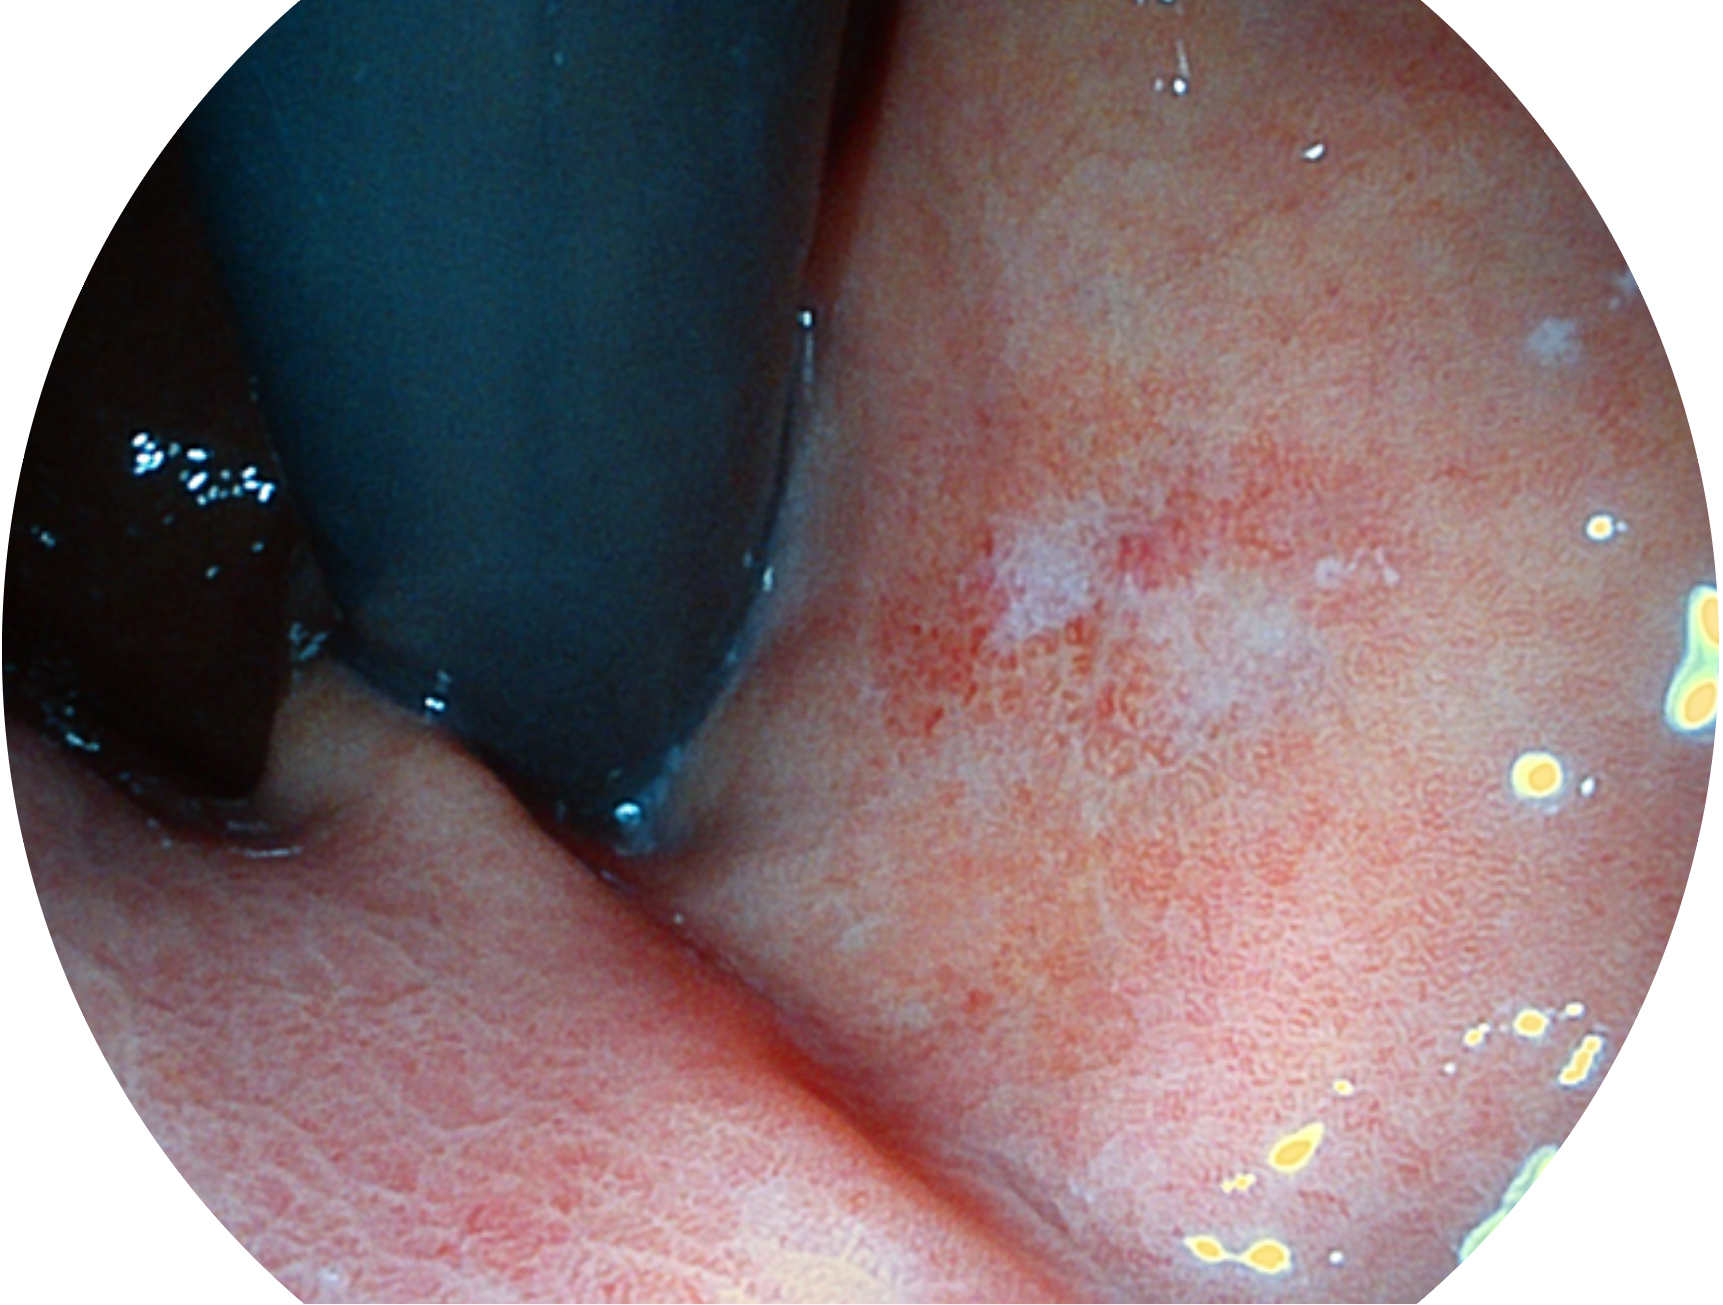

16877太阳集团新开发的内镜染色技术,主要是基于多波长LED 光源的开发,VLS-55Q 四波长LED 光源是由四个不同颜色的LED光按照相应照明模式所规定的特定发光比例进行合束后形成,合束后形成的照明光的光谱由红光、绿光、蓝光及蓝紫光这四个不同的波段范围构成。具有更高光谱自由度,通过光谱比例的控制,实现了聚谱成像技术,英文全称为“Spectral Focused Imaging, SFI”,缩写为“SFI”和光电复合染色成像技术,英文全称为“Versatile Intelligent Staining Technology, VIST”,缩写为“VIST”。